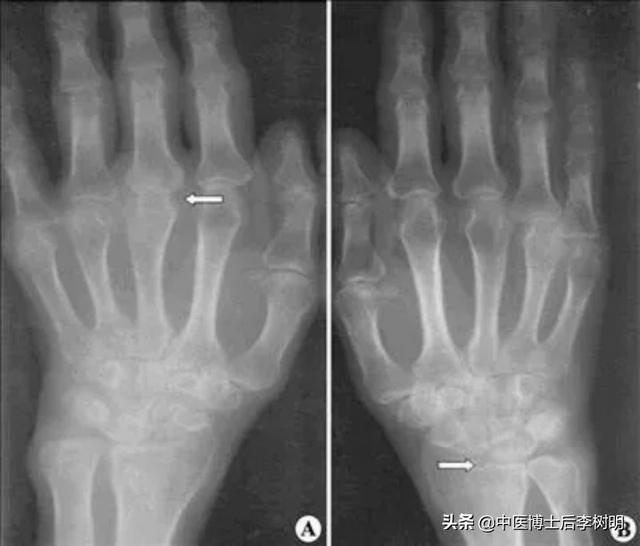

医生通过病史、体格检查和受影响关节的X光片来诊断骨关节炎。

在片子中,医生可以观察到关节的缝隙变窄了,靠近关节的骨头出现硬化,以及出现小空腔一样的囊性变。在关节的边缘周围有骨刺的形成。部分的病人还可以看到关节肿胀,以及关节内的游离体等等。